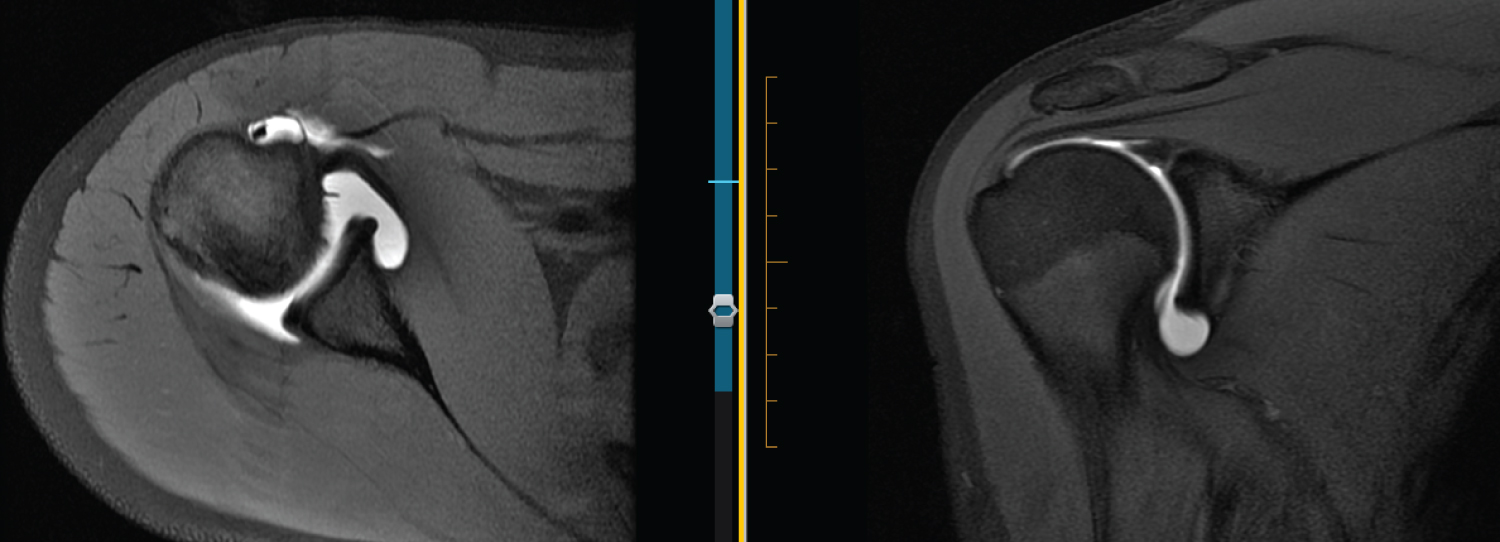

Figure 1: 16 F R MRA. From left to right: Axial T1 FS, Coronal T1 FS, and T1 FS ABER. Labrum looks blunted, rounded and undefined on axial. Nearly absent on coronal. Intact IGHL on ABER and intact labrum. View Figure 1

Figure 2: 16 F R MRA. IGHL may be overlying labrum on axial view as coronal view shows thickened IGHL very well. Otherwise, labrum appears undefined. ABER view looks normal. View Figure 2